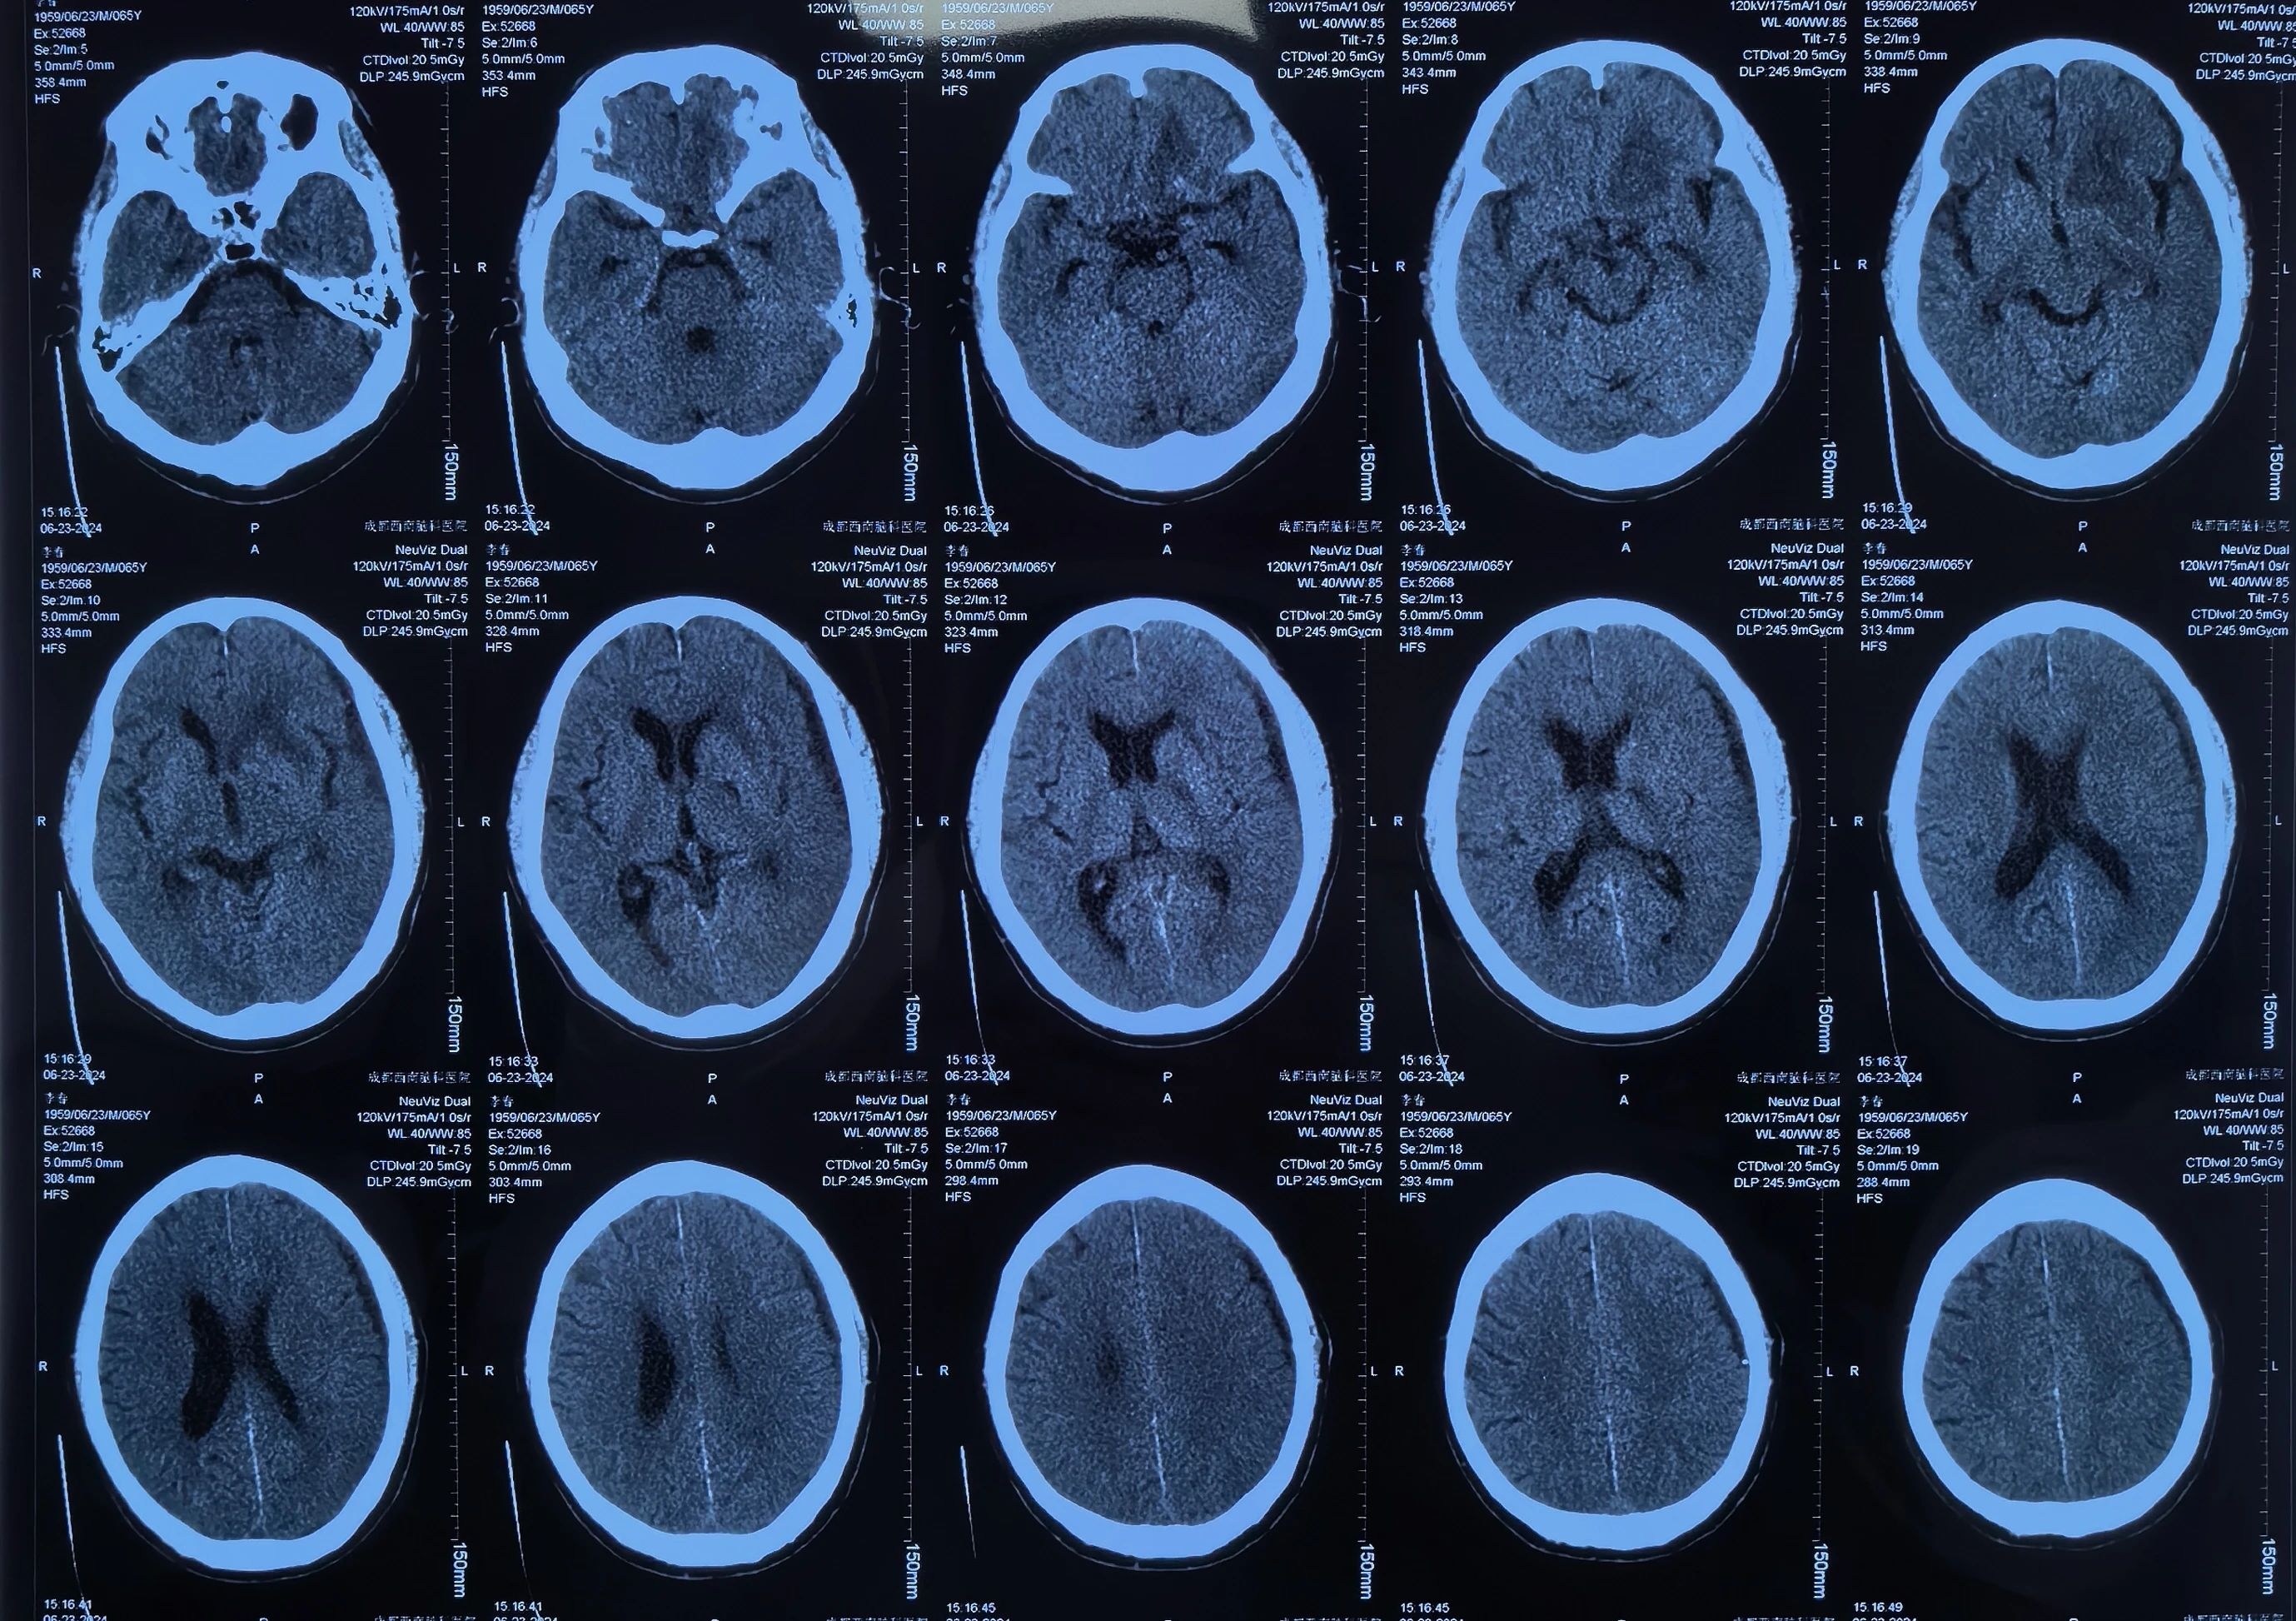

李先生手术后

李先生术后引流中

术后李先生自觉头痛明显减轻,术后第三天复查头颅CT提示:硬膜下血肿基本清除,脑移位恢复正常。